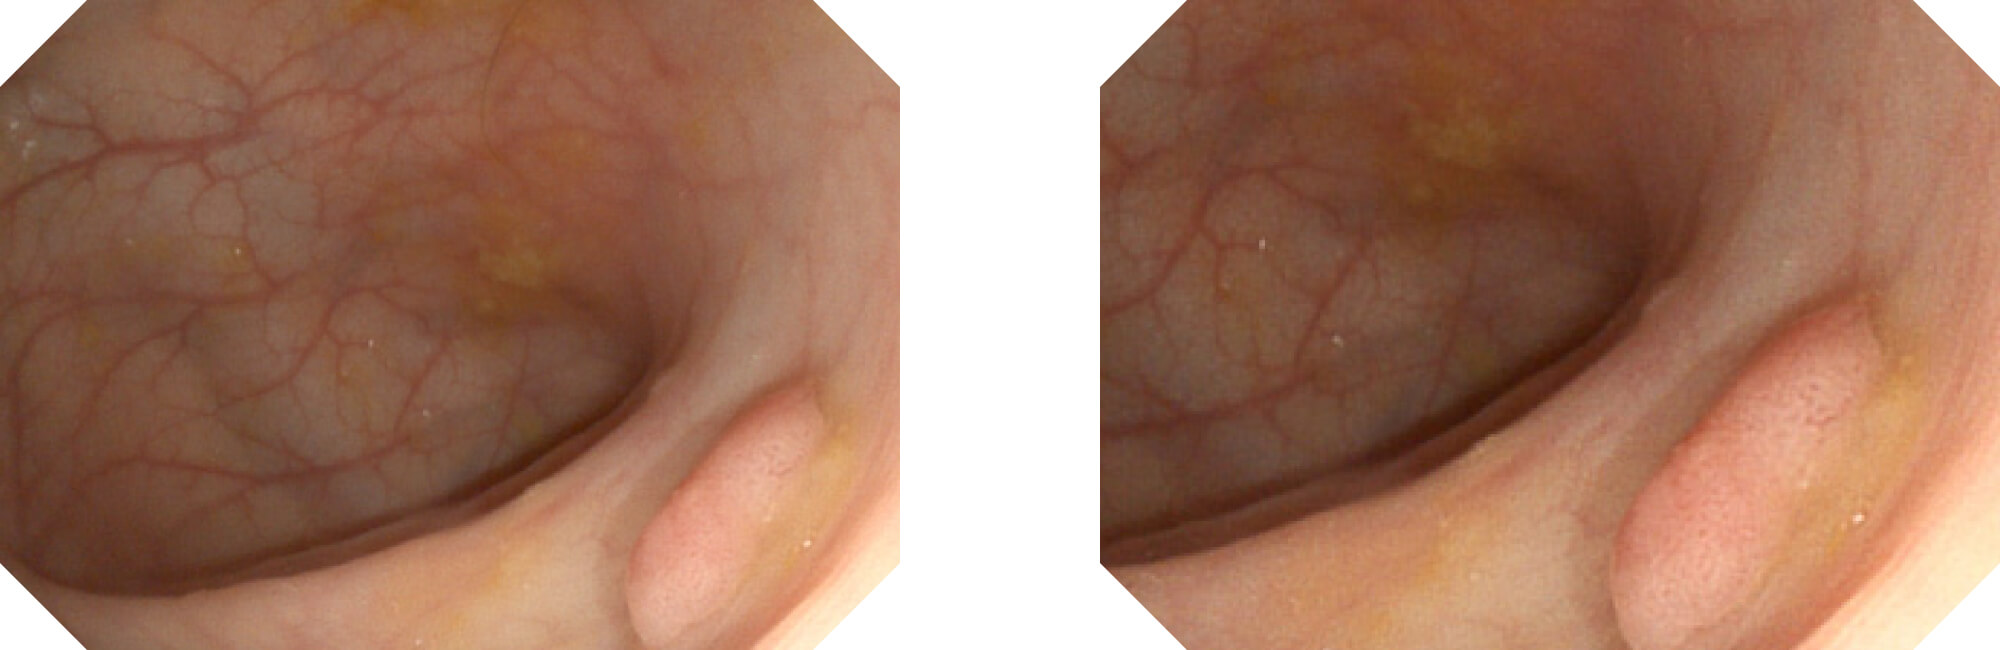

(Versatile Intelligent Staining Technology)

利用了血红蛋白在不同波长吸收下系数不同的原理,设计的一种光学域滤波和数字域滤波结合的染色技术,既保证了图像亮度,又可增强黏膜血管的对比度,充分凸显早期病变的细微结构变化,为临床疾病的观察诊断提供更丰富的参考信息。